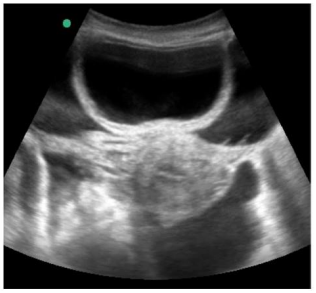

Uma paciente de 55 anos de idade, internada na UTI em razão de quadro de cirrose alcoólica com hemorragia digestiva alta por varizes esofágicas.

Enunciado 4863547-1

Diante do achado evidenciado na ultrassonografia abdominal, o plantonista procedeu à paracentese guiada por ultrassonografia para diagnóstico diferencial, com a qual pretendia diagnosticar